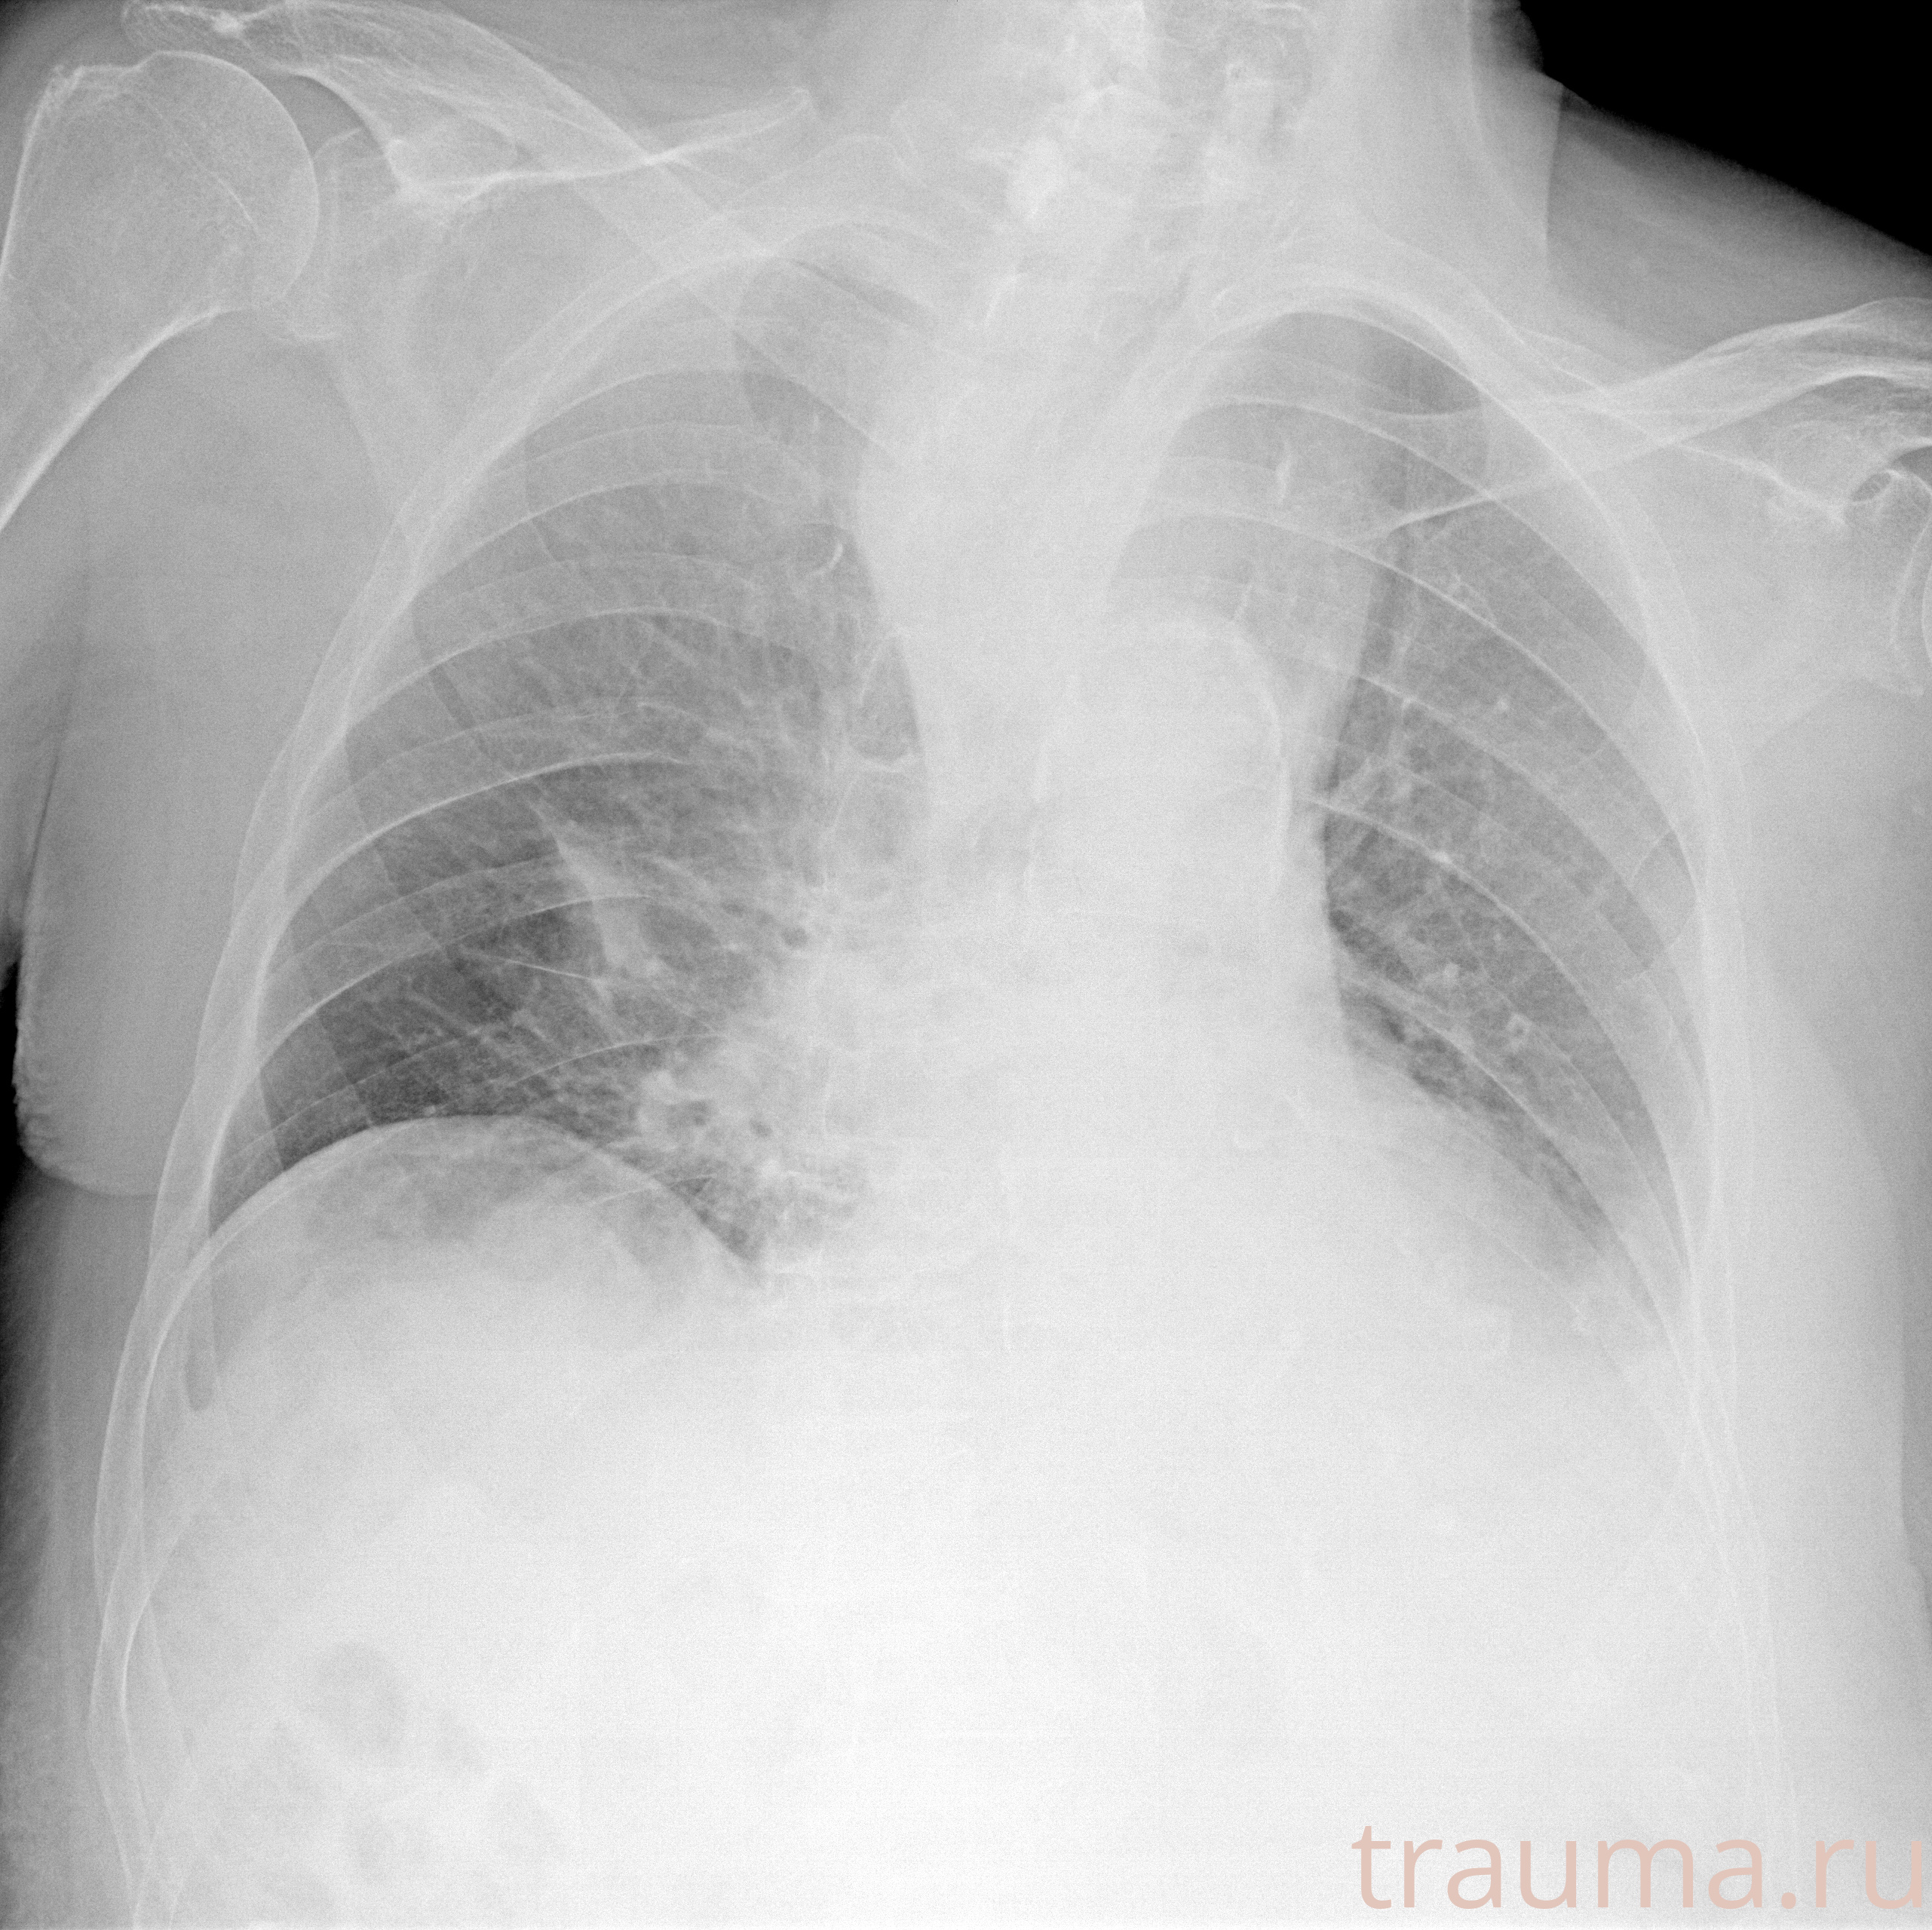

Рентген на дому: по вашему адресу приезжает врач-рентгенолог, травматолог-ортопед с мобильным рентгеновским аппаратом, проводит диагностику травмы или заболевания, делает необходимые рентгенограммы, дает рекомендации по дальнейшему лечению. Получить качественные снимки в домашних условиях возможно благодаря уникальной методике, разработанной МосРентген Центром для института  Склифосовского

при переломе шейки бедра и пневмонии от компании МосРентген Центр - партнера Института имени Склифосовского